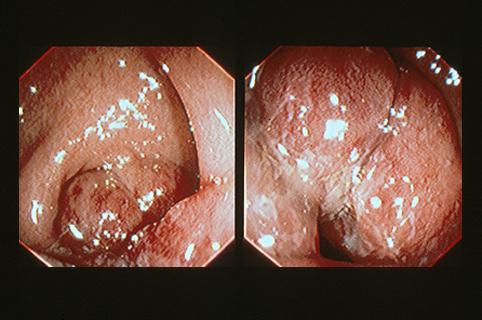

疾病(病理主体)的分类恶性淋巴系肿瘤/恶性淋巴瘤

部位(按器官分)大肠/直肠

检查方法内窥镜

肿瘤最大直径40以上